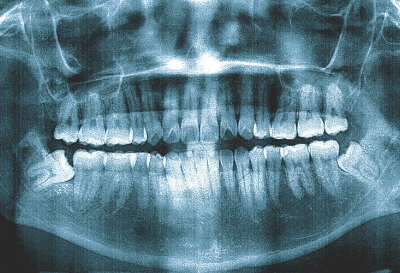

当院では通常の抜歯に加えて親知らずの抜歯も可能です。親知らずは一番奥に生えてくることで磨き残しができやすい歯です。歯の生え方によっては抜歯が最も難しい歯ですがむし歯ができる前に治療をする必要があります。親知らずの抜歯でも口腔外科認定医の院長が対応しますのでご相談ください。親知らずを抜くことでむし歯のリスクを抑え第二大臼歯を守ることができます。

精密検査によって残せない歯を診断します。親知らずであれば深さや神経との距離をCTで観察しリスクなどを判定します。

通常の抜歯であってもCTを撮影し根の形態を確認することで抜歯が行いやすくなります。痛みに配慮しながら口腔外科認定医の院長が抜歯を行います。